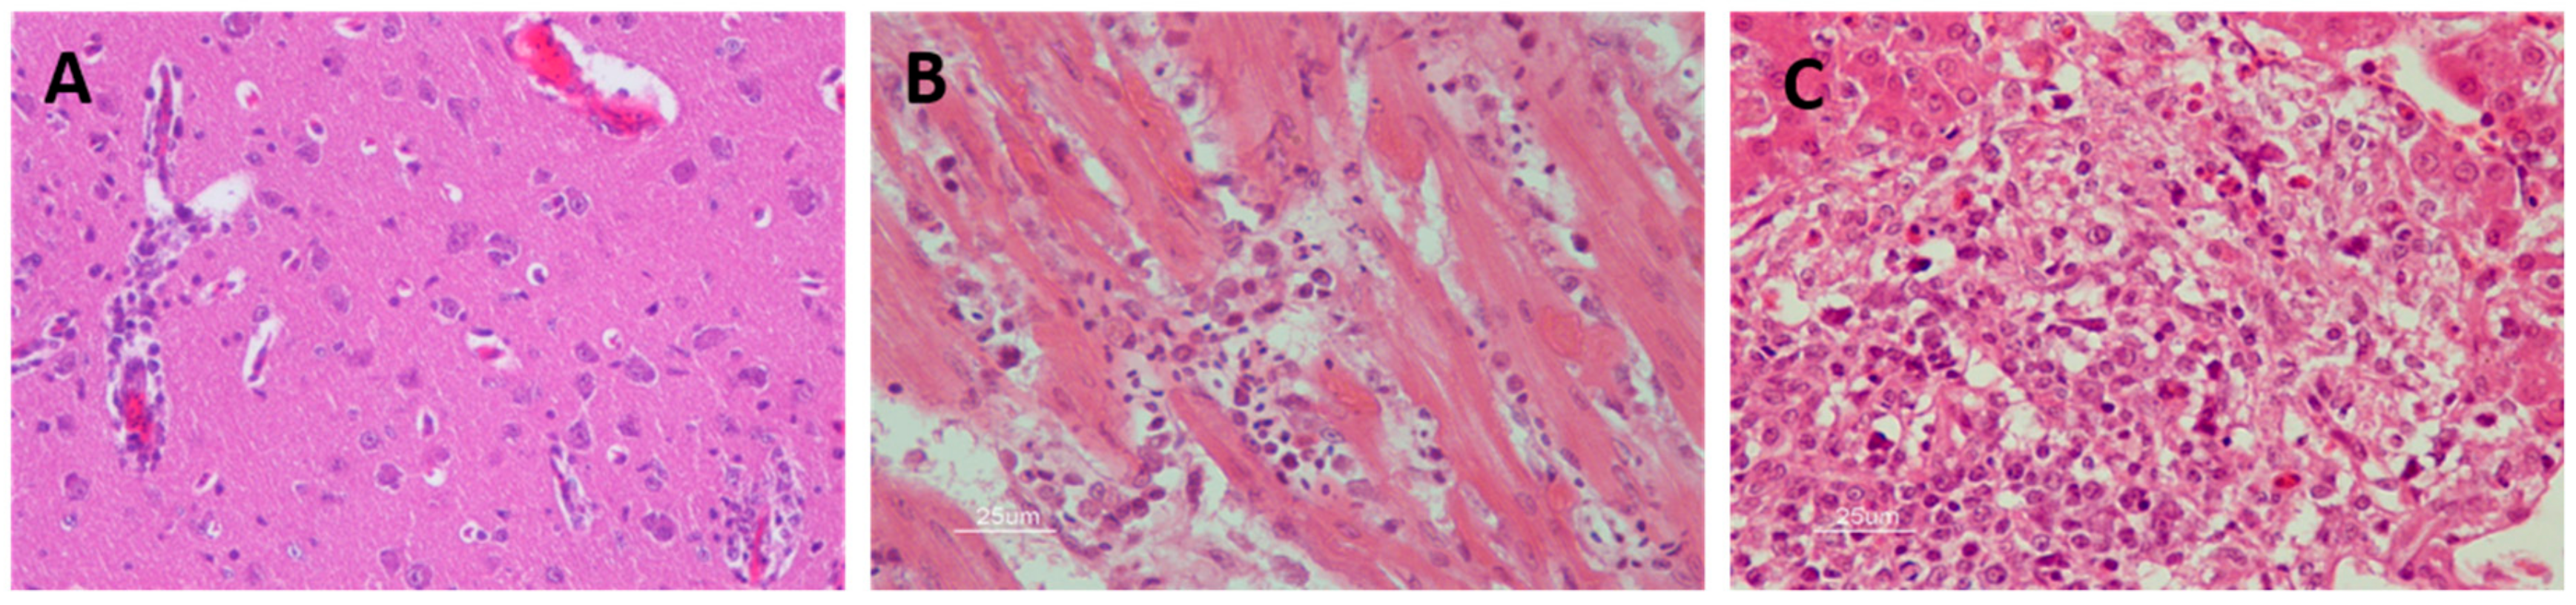

Among the histopathological findings of the affected organs (Figure 5), central nervous system lesions are mainly characterized by hemorrhages in the brain [81,82,83], mild perivascular cuffs consisting of lymphocytes and plasma cells, scattered individual necrotic neurons, lymphoplasmacytic, and histiocytic meningoencephalitis characterized by gliosis and glial nodules [47,48,59]. The main findings in the heart are lymphoplasmacytic and histiocytic myocarditis with myocardial necrosis, concurrent fibrosis, sometimes with thrombi, hypereosinophilia of cardiomyocytes, myocytolysis, nuclear swelling, pyknosis, loss of striations, myofiber degeneration, and hemorrhages [70,80,84]. Liver lesions include multifocal randomly distributed granulomatous and lymphohistiocytic hepatitis, with mild to moderate coagulative hepatocellular necrosis and deposition of fibrin [75]. The spleen is also affected by WNV infection, where multifocal lymphocytic necrosis occurs characterized by the presence of karyorrhectic nuclear debris [75,81]. Significant histopathological abnormalities present in the kidney are mild multifocal proximal tubular necrosis and mild to moderate lymphoplasmacytic interstitial nephritis that can occasionally be perivascular [70,75,85]. Ocular lesions are also common in WNV-infected birds. These lesions consist of the disarray of the retinal pigmented epithelial cell layer, pectenitis, choroidal or retinal inflammation, cellular necrosis, muscular degeneration in the iris, mild optic neuritis, impaired vision, and even blindness [47,76,86,87,88]. Other less common described lesions include pancreatitis, pulmonary edema, infiltration of lymphocytes, plasma cells and histiocytes in the intestinal tract, necrotizing mucosal duodenitis, myofiber degeneration with lymphoplasmacytic inflammation, and fibrosis in skeletal muscle [89,90].

Figure 5.

Histopathological findings in WNV-infected red-legged partridge. (A) Moderate gliosis, and lymphoplasmacytic and histiocytic perivascular cuffs observed in the brain. (B) Extensive myocardial degeneration and necrosis with inflammatory infiltrate composed of lymphocytes, plasma cells, and histiocytes observed in the heart. (C) Extensive liver necrosis with predominantly lymphoplasmacytic infiltrate. Images courtesy of Dr. U. Höfle and Dr. V. Gamino.